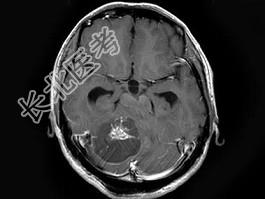

单项选择题男,33岁, 阵发性头痛伴呕吐行走不稳1个月,MRI平扫及增强扫描如图, 最可能的诊断是 ( )

A、右小脑星形细胞瘤

B、右小脑脓肿

C、右小脑血管母细胞瘤

D、转移瘤